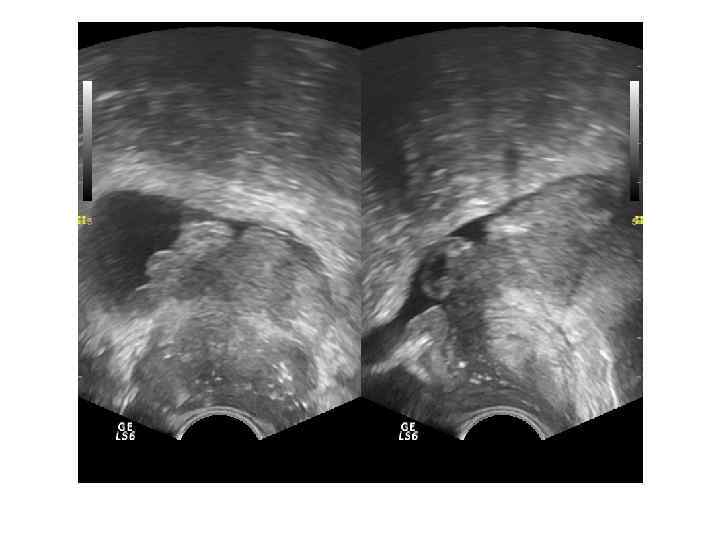

Абсцесс предстательной железы имеет достаточно характерную ультразвуковую картину: одно или несколько объемных образований в паренхиме простаты чаще округлой или овоидной формы с толстой слоистой стенкой и неоднородным жидкостным содержимым, с усилением сосудистого рисунка по периферии. ТРУЗИ болезненно!!

Поражение парапростатической клетчатки При распространении воспалительного процесса на парапростатическую клетчатку сонографически можем видеть в ней гипоэхогенные, гетерогенные зоны с неровным, нечетким контуром, аваскулярные – зоны воспалительной инфильтрации, капсула простаты частично не прослеживается, возможно формирование парапростатической флегмоны.